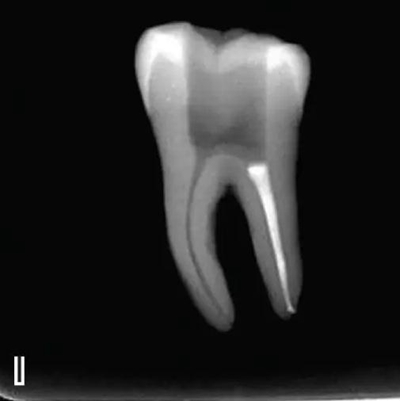

在完成根尖段的充填后,使用熱塑牙膠注射儀對根管中上段進(jìn)行分層充填,一般分2~3次完成充填,每次充填均使用相應(yīng)直徑大小的垂直加壓器進(jìn)行加壓。拍片確認(rèn)充填效果(圖8)。

圖8 熱牙膠根中上段的充填,A、B.注射儀注射中段熱牙膠

C、D.垂直加壓器加壓 E、F.注射儀繼續(xù)注射上段熱牙膠

G、H.垂直加壓器加壓 I、J.完成根中上段的充填